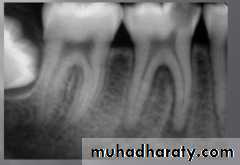

radiograph: X-ray examination with digital zoom and color contrasting ability permits a deeper insight to the pulp canal.